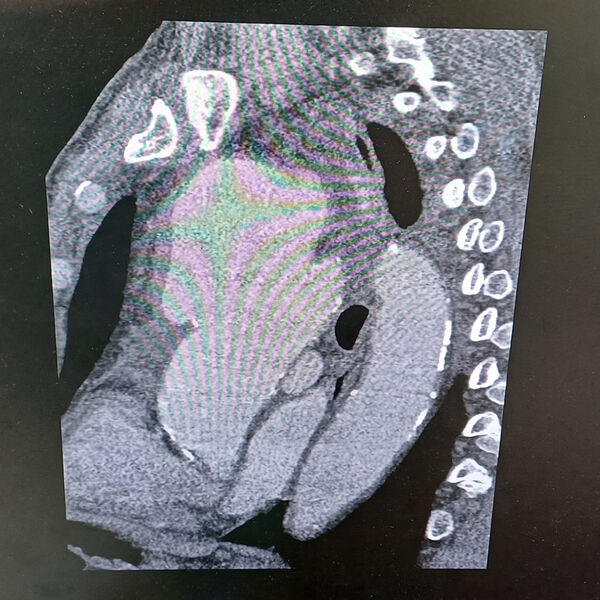

«Компьютерная томограмма подтвердила выпячивание аорты размером 9 на 9 сантиметров. Гигантская мешотчатая аневризма, больше, чем гусиное яйцо», — рассказал заведующий отделением №5 Рязанского кардиодиспансера Сергей Загородний.

По словам специалиста, аневризма сдавливала все близлежащие органы и ткани: трахеи, бронхи, верхнюю полую вену.